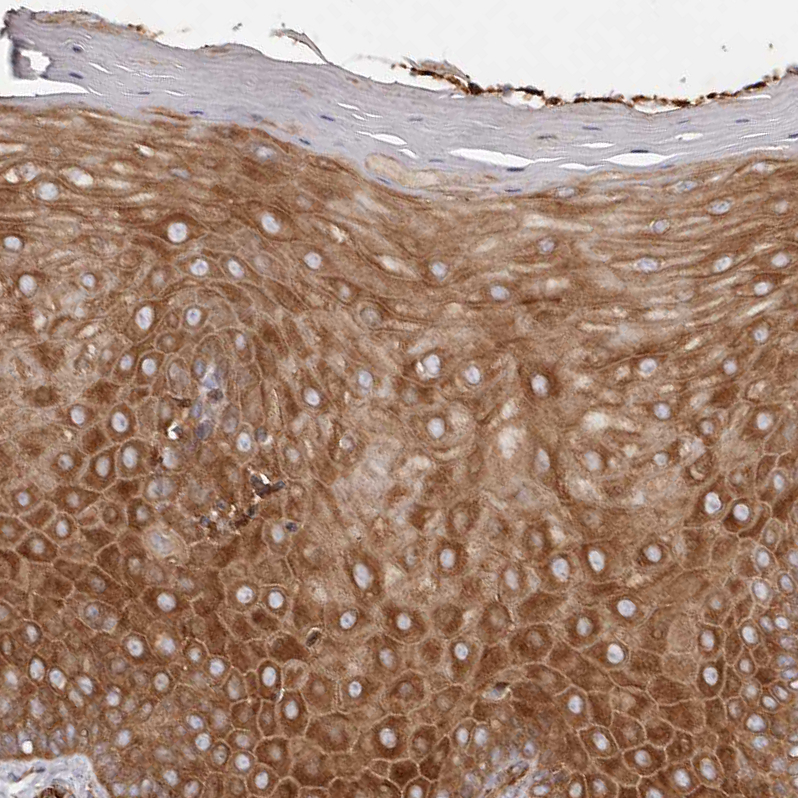

Immunohistochemical staining of human pancreas shows strong cytoplasmic positivity in exocrine glandular cells.